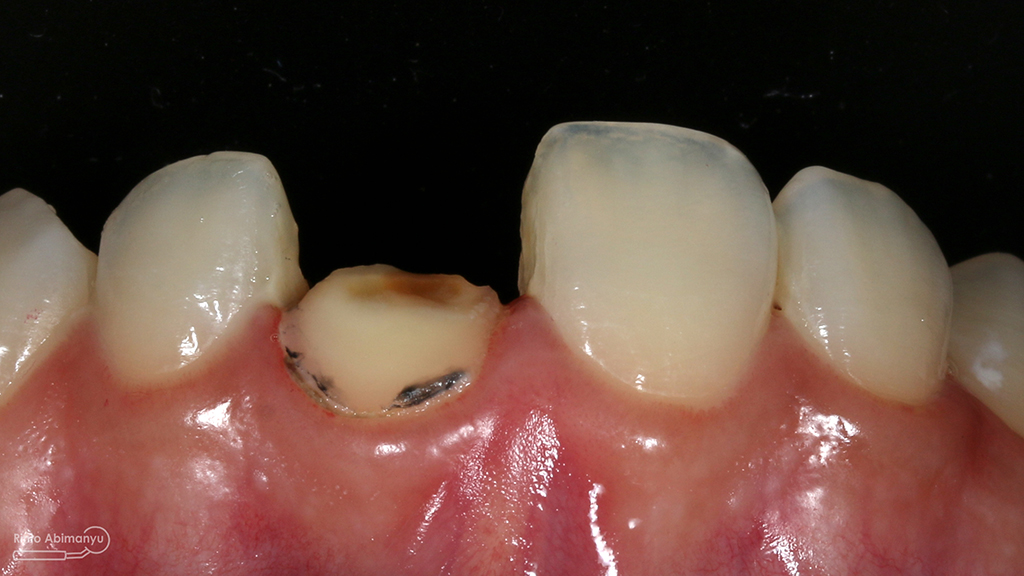

Begini kondisi klinis saat datang…

Foto klinis gigi-gigi anterior yang mengalami fraktur

Dari pemeriksaan radiografis lokasi fraktur menyerempet kamar pulpa pada ketiga gigi tersebut… Saya sampaikan kepada pasien bahwa ketiga gigi tersebut memerlukan perawatan saluran akar terlebih dahulu baru kemudian dilanjutkan dengan restorasi indirek… kenapa saya pilih restorasi indirek? Pertimbangannya adalah sisa struktur mahkota gigi yang ada bila hanya di “sambung” dengan restorasi direk dalam jangka panjang rentan mengalami kerusakan, yang kedua pemilihan warna akan lebih maksimal pada kasus ini…. Pasien setuju dengan rencan perawatan yang saya jelaskan…